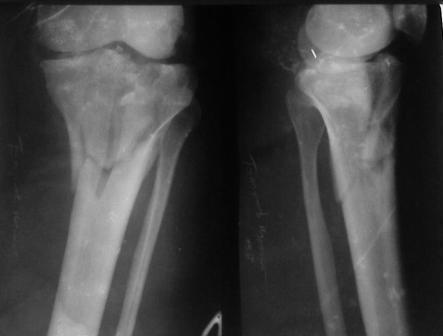

Недавно поступила больная через 1,5- 2 месяца.

Уважаемый Абдурашид. Если нет противопоказаний , то из оперативных способов, я бы рекомендовал следующие: Полное замещение наружного мыщелка аллотрансплантатом либо открытая репозиция с элевацией и замещение дефекта ауто или аллокостью. В Ваших условиях , я бы рекомендовал второй способ. Во-время элевации необходимо разъединить фрагменты со стороны сустава ( надсечь скальпелем по линиям перелома, а затем тонким остеотомом их разъединить. При помощи долота произвести неполную остеотомию ( захватите не менее 1,5 - 2 см губчатой кости и поднять фрагменты, визуально отрепонировать и фиксировать 2-3 спицами. Дефект заместить костным ауто или аллатрансплантатом. Окончательная стабилизация пластиной ( лучше с угловой стабильностью, либо АВФ - позволит спокойно устранить угловую деформацию.